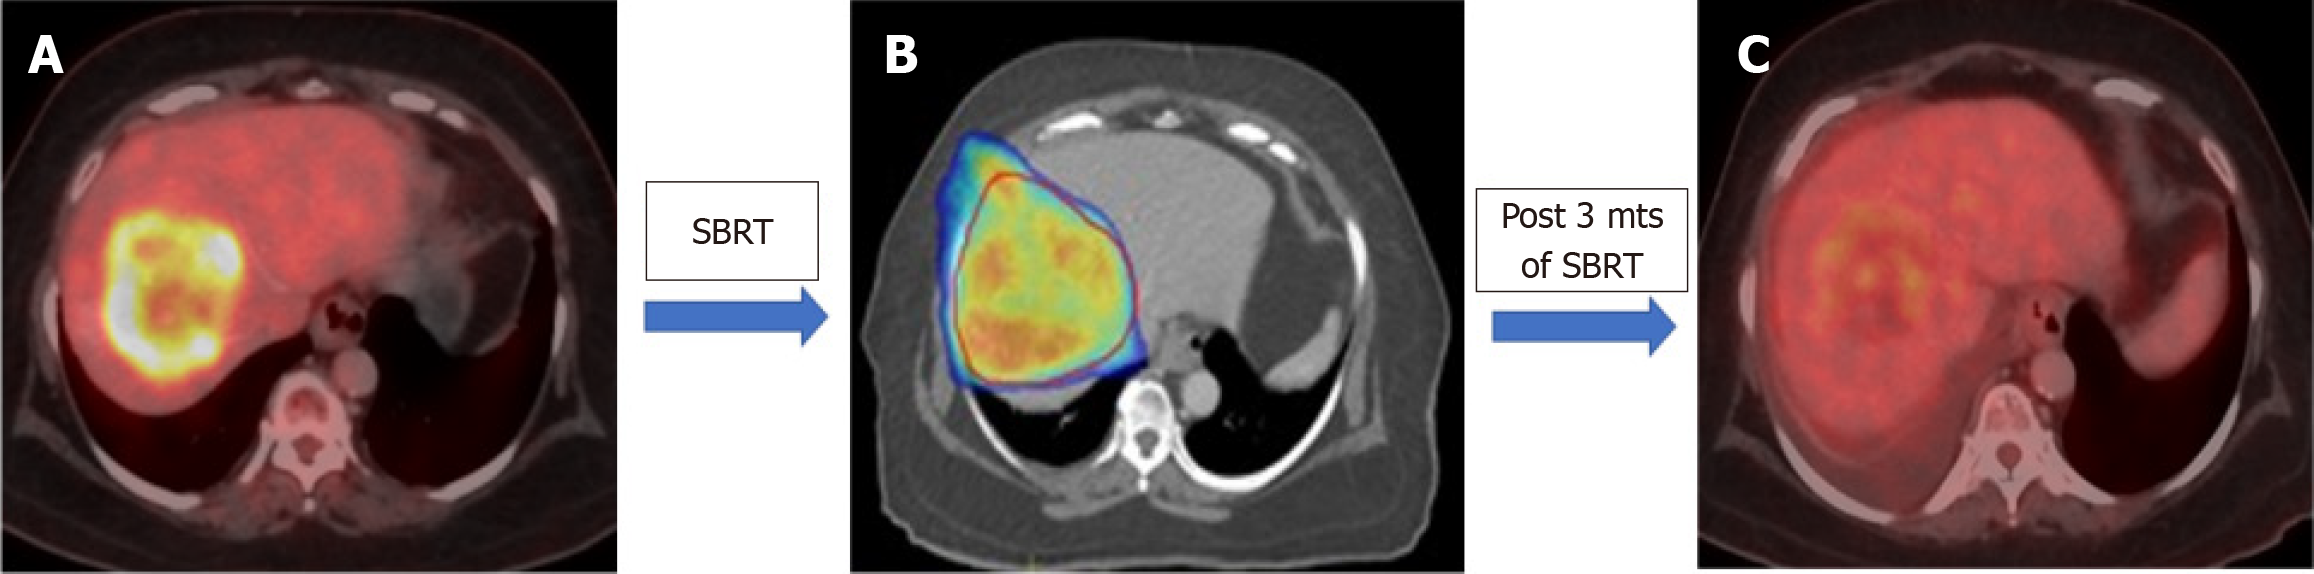

Figure 1 Post stereotactic body radiation therapy response in a case of intrahepatic cholangiocarcinoma.

A: Pre-stereotactic body radiation therapy (SBRT) positron emission tomography/computed tomography: Metabolically active ill-defined hypodense lesions with heterogeneous peripheral arterial enhancement and central necrotic changes involving segments VIII and V suggestive of intrahepatic cholangiocarcinoma; B: Stereotactic body radiation therapy colorwash; C: Positron emission tomography/computed tomography (post SBRT and three cycles of Gemcitabine /cisplatin base chemotherapy): There is significant interval reduction in metabolic activity of the primary lesion along with mild interval reduction in size of the lesion with appearance of central necrotic changes. SBRT: Stereotactic body radiation therapy.